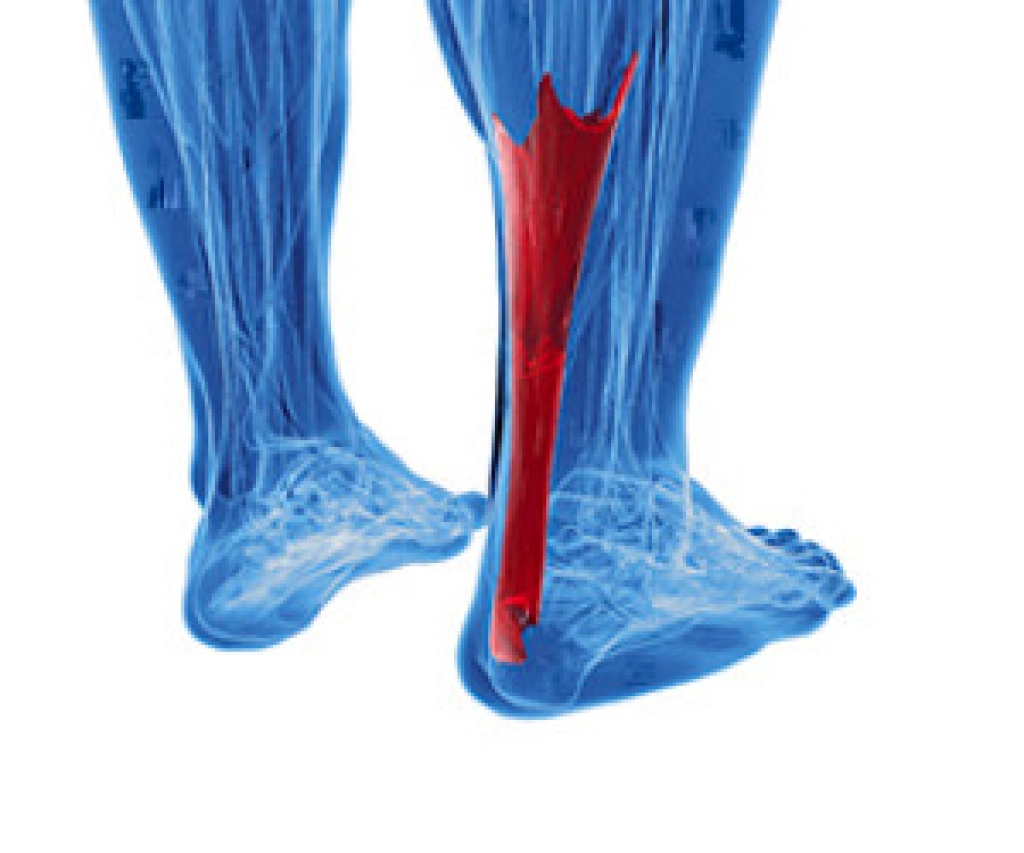

Symptoms of an Achilles Tendon Injury

The Achilles tendon is considered to be the largest tendon in the body. Its function is to connect the heel to the calf muscles, and it is important for this tendon to maintain its flexibility and strength. It is typically put under pressure for the majority of the day as walking or running and jumping activities are completed. If an injury should occur to the Achilles tendon, it may become swollen and inflamed. This type of injury is known as tendonitis. A common symptom that can be associated with this condition may be pain in the heel and surrounding areas. If a rupture should occur, you may hear a popping sound emanating from the back of the heel. This is typically indicative of a serious injury, and medical attention should be sought as quickly as possible. If you have any pain in the back of the calf or in the heel, please consult with a podiatrist who can properly diagnose and treat an Achilles tendon injury.

What Is the Achilles Tendon?

The Achilles tendon is a tendon that connects the lower leg muscles and calf to the heel of the foot. It is the strongest tendon in the human body and is essential for making movement possible. Because this tendon is such an integral part of the body, any injuries to it can create immense difficulties and should immediately be presented to a doctor.

What Are the Symptoms of an Achilles Tendon Injury?

There are various types of injuries that can affect the Achilles tendon. The two most common injuries are Achilles tendinitis and ruptures of the tendon.

Achilles Tendinitis Symptoms

• Inflammation

• Dull to severe pain

• Increased blood flow to the tendon

• Thickening of the tendon

Rupture Symptoms

• Extreme pain and swelling in the foot

• Total immobility